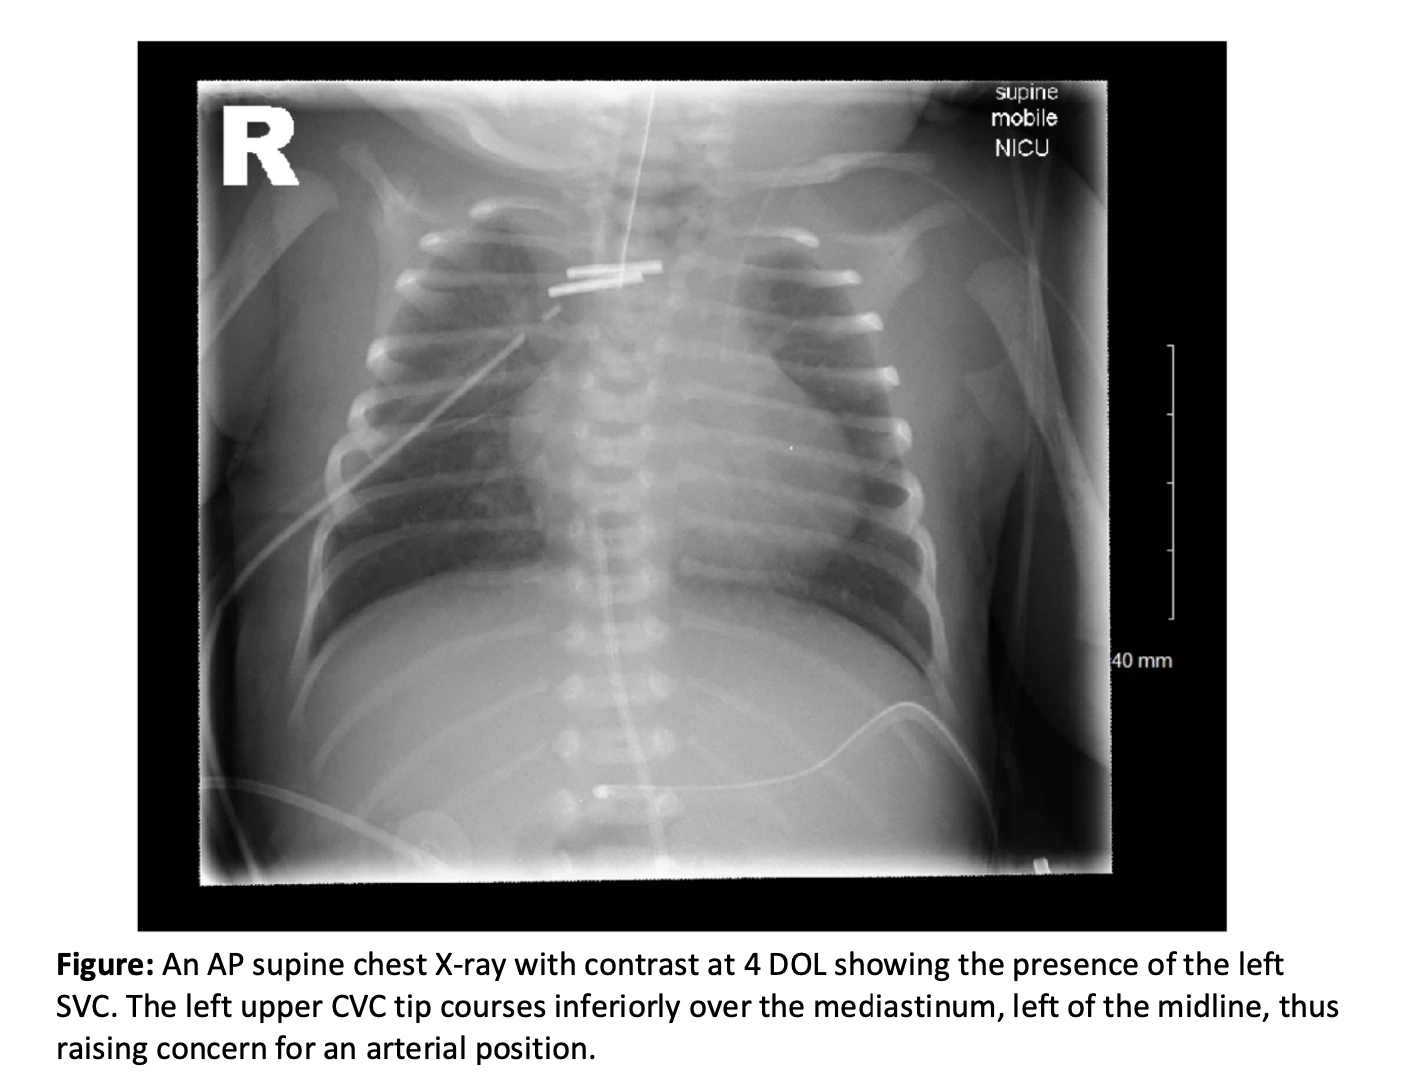

Case presentation summary: A male infant was born at 33 weeks’ gestation via emergency caesarean to healthy, non-consanguineous Nigerian parents, due to intrauterine growth restriction, cerebral redistribution, and abnormal Dopplers. Maternal history included gestational diabetes and pre-eclampsia. He required resuscitation at birth (Apgar scores of 1, 8, 9). Failed nasogastric tube insertion raised immediate concern for OA. Examination revealed unilateral pre-axial polydactyly and imperforate anus. He was transferred at 6 hours of life to a regional surgical centre, where imaging confirmed OA with TOF, abnormal bowel gas, and distal colonic narrowing. On day 0 of life (DOL), he underwent thoracotomy with TOF ligation, gastrostomy for long-gap OA, and sigmoid-descending colostomy. Re-anastomosis and ‘pull-through’ surgery due to long oesophageal gap is planned for 3 months of life. VACTERL association was diagnosed postnatally based on tracheoesophageal, anorectal, limb and later cardiac anomalies. On DOL4, chest X-ray (Figure 1) following central venous catheter (CVC) insertion unexpectedly revealed a persistent left SVC (PLSVC). Subsequent echocardiography confirmed bilateral SVCs, a vascular anomaly scarcely associated with VACTERL. This finding complicated CVC placement and highlighted the importance of early cardiac imaging in neonates. Cranial and renal ultrasounds, and spinal X-ray were normal. The extra digit autoamputated after bedside clipping (DOL 14). Chromosomal microarray was normal. Spinal ultrasound and micturating cystourethrogram are pending to complete VACTERL screening.

Learning points discussion: Cardiac anomalies present in 40–80% of VACTERL cases and contribute significantly to associated morbidity and mortality. Our case highlights bilateral SVCs, an exceptional but crucial finding, identified only after repeated concerns about CVC positioning. PLSVC is the most common thoracic venous anomaly, occurring in 0.3% of the general population and 3-11% of congenital heart disease patients. Its association with VACTERL is uncommonly reported, and true prevalence remains unknown. Thus, suggesting such vascular anomalies may be under-recognised in the VACTERL spectrum. This diagnostic gap has practical implications.

In our case, the missed identification of bilateral SVCs led to multiple unnecessary line insertions. Diagnostic challenges are only exacerbated by its typical asymptomatic presentation. Additionally, prenatal VACTERL diagnosis remains challenging and does not consistently improve outcomes. Instead, it often results in earlier delivery (by 2 weeks) and higher neonatal mortality risk. This case illustrates the phenotypic diversity of VACTERL, reinforces the need for comprehensive postnatal anomaly screening, and highlights the value of early cardiac imaging when multiple congenital anomalies are present. A PLSVC should be considered a necessary differential when CVCs appear to track unusually over the left thorax.